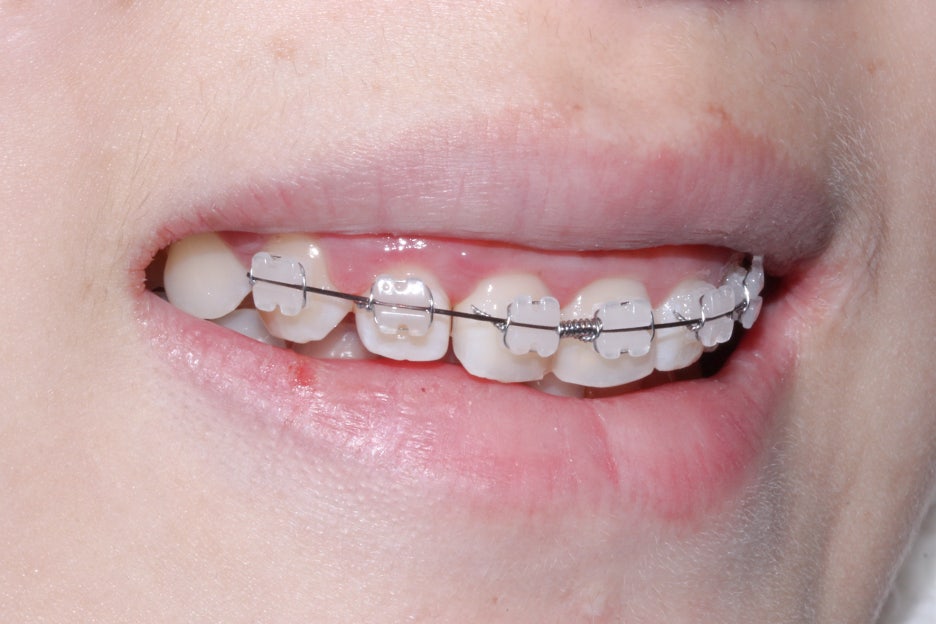

교정 시작 후 약 5개월 경과 후 모습입니다.

삐뚤거리던 전치부의 치아들이 가지런하게

배열된 것을 확인할 수 있는데요,

나비치아 증상을 보이던 중절치도

바른 치축으로 교정된 모습입니다.

전치부를 옆에서 보면 위처럼

유난히 돋보이던 중절치의 회전 증상이

크게 완화된 모습을 볼 수 있는데요,

왜소치처럼 보이던 측절치도 상대적으로

중절치가 가지런해지면서 작아보이던

증상도 개선된 모습입니다.

옥니교정을 위해서 지난 5개월 간 위와 같은

장치를 사용하여 중절치의 치축을 돌리는 과정을 진행하였는데요,

뻐드러진 중절치의 바깥면을 설측으로 당겨오기 위해

파워체인을 걸어 당기는 힘을 지속적으로 가하였습니다.

또한 중절치가 마주보고 있는 부분은 오픈코일스프링을 사용하여

공간을 넓혀주어 치열이 자연스러운 U자 모양을 형성할 수 있도록 하였는데요,